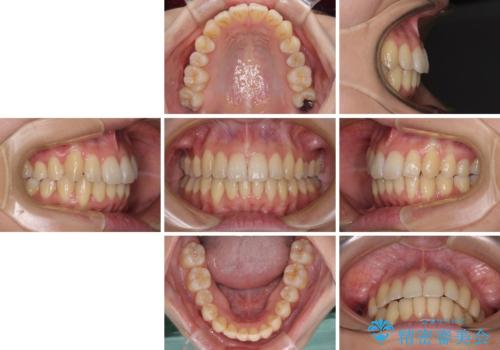

突出した印象のあった前歯をきれいに引っ込めることができたので、口が閉じやすくなり、横顔の印象をスッキリとさせることができました。

でこぼこしていて磨きにくかった歯と歯の間も清掃しやすくなり、患者様には大変満足していただきました。